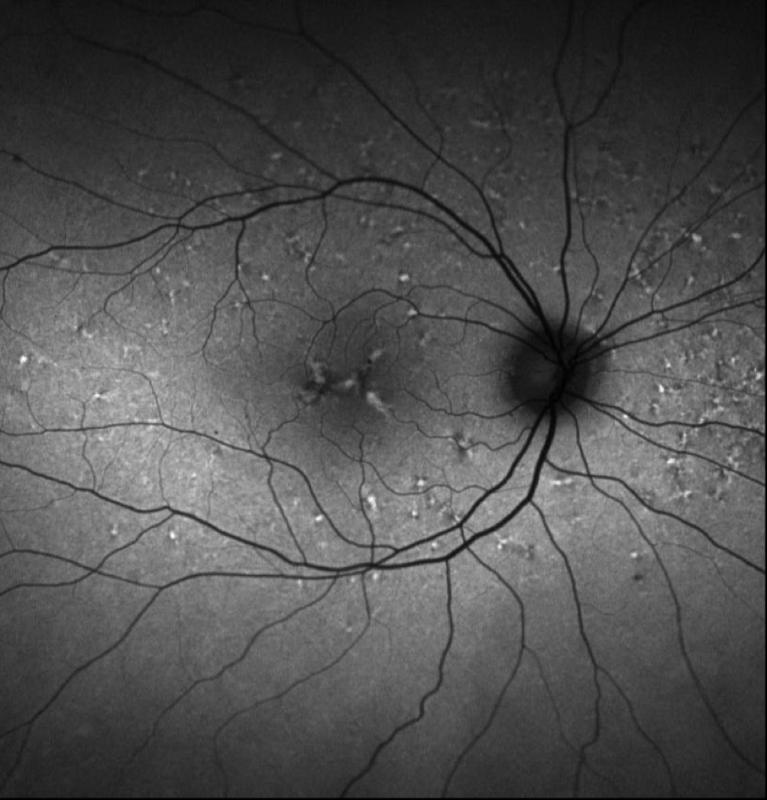

Clinical Practice Today : Advances in OCT

In the early 1990s, optical coherence tomography (OCT) emerged as a revolutionary new technology in the field of ophthalmology.